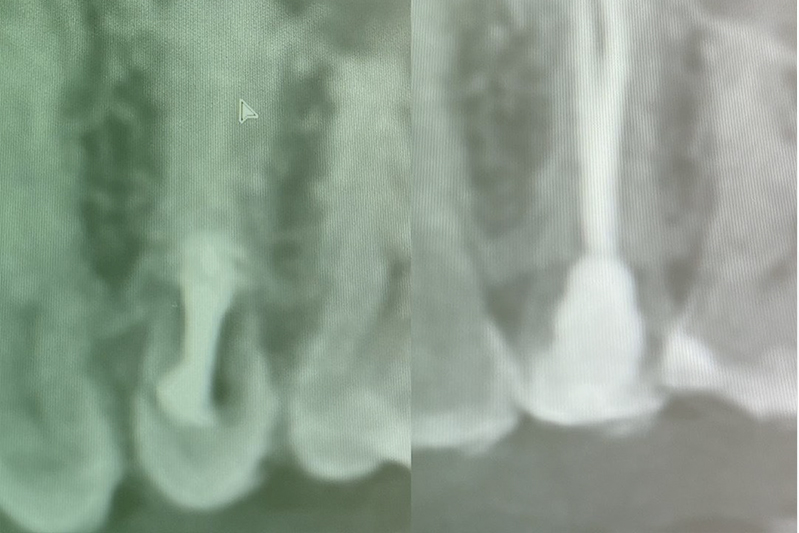

Клинический случай. Эндодонтия